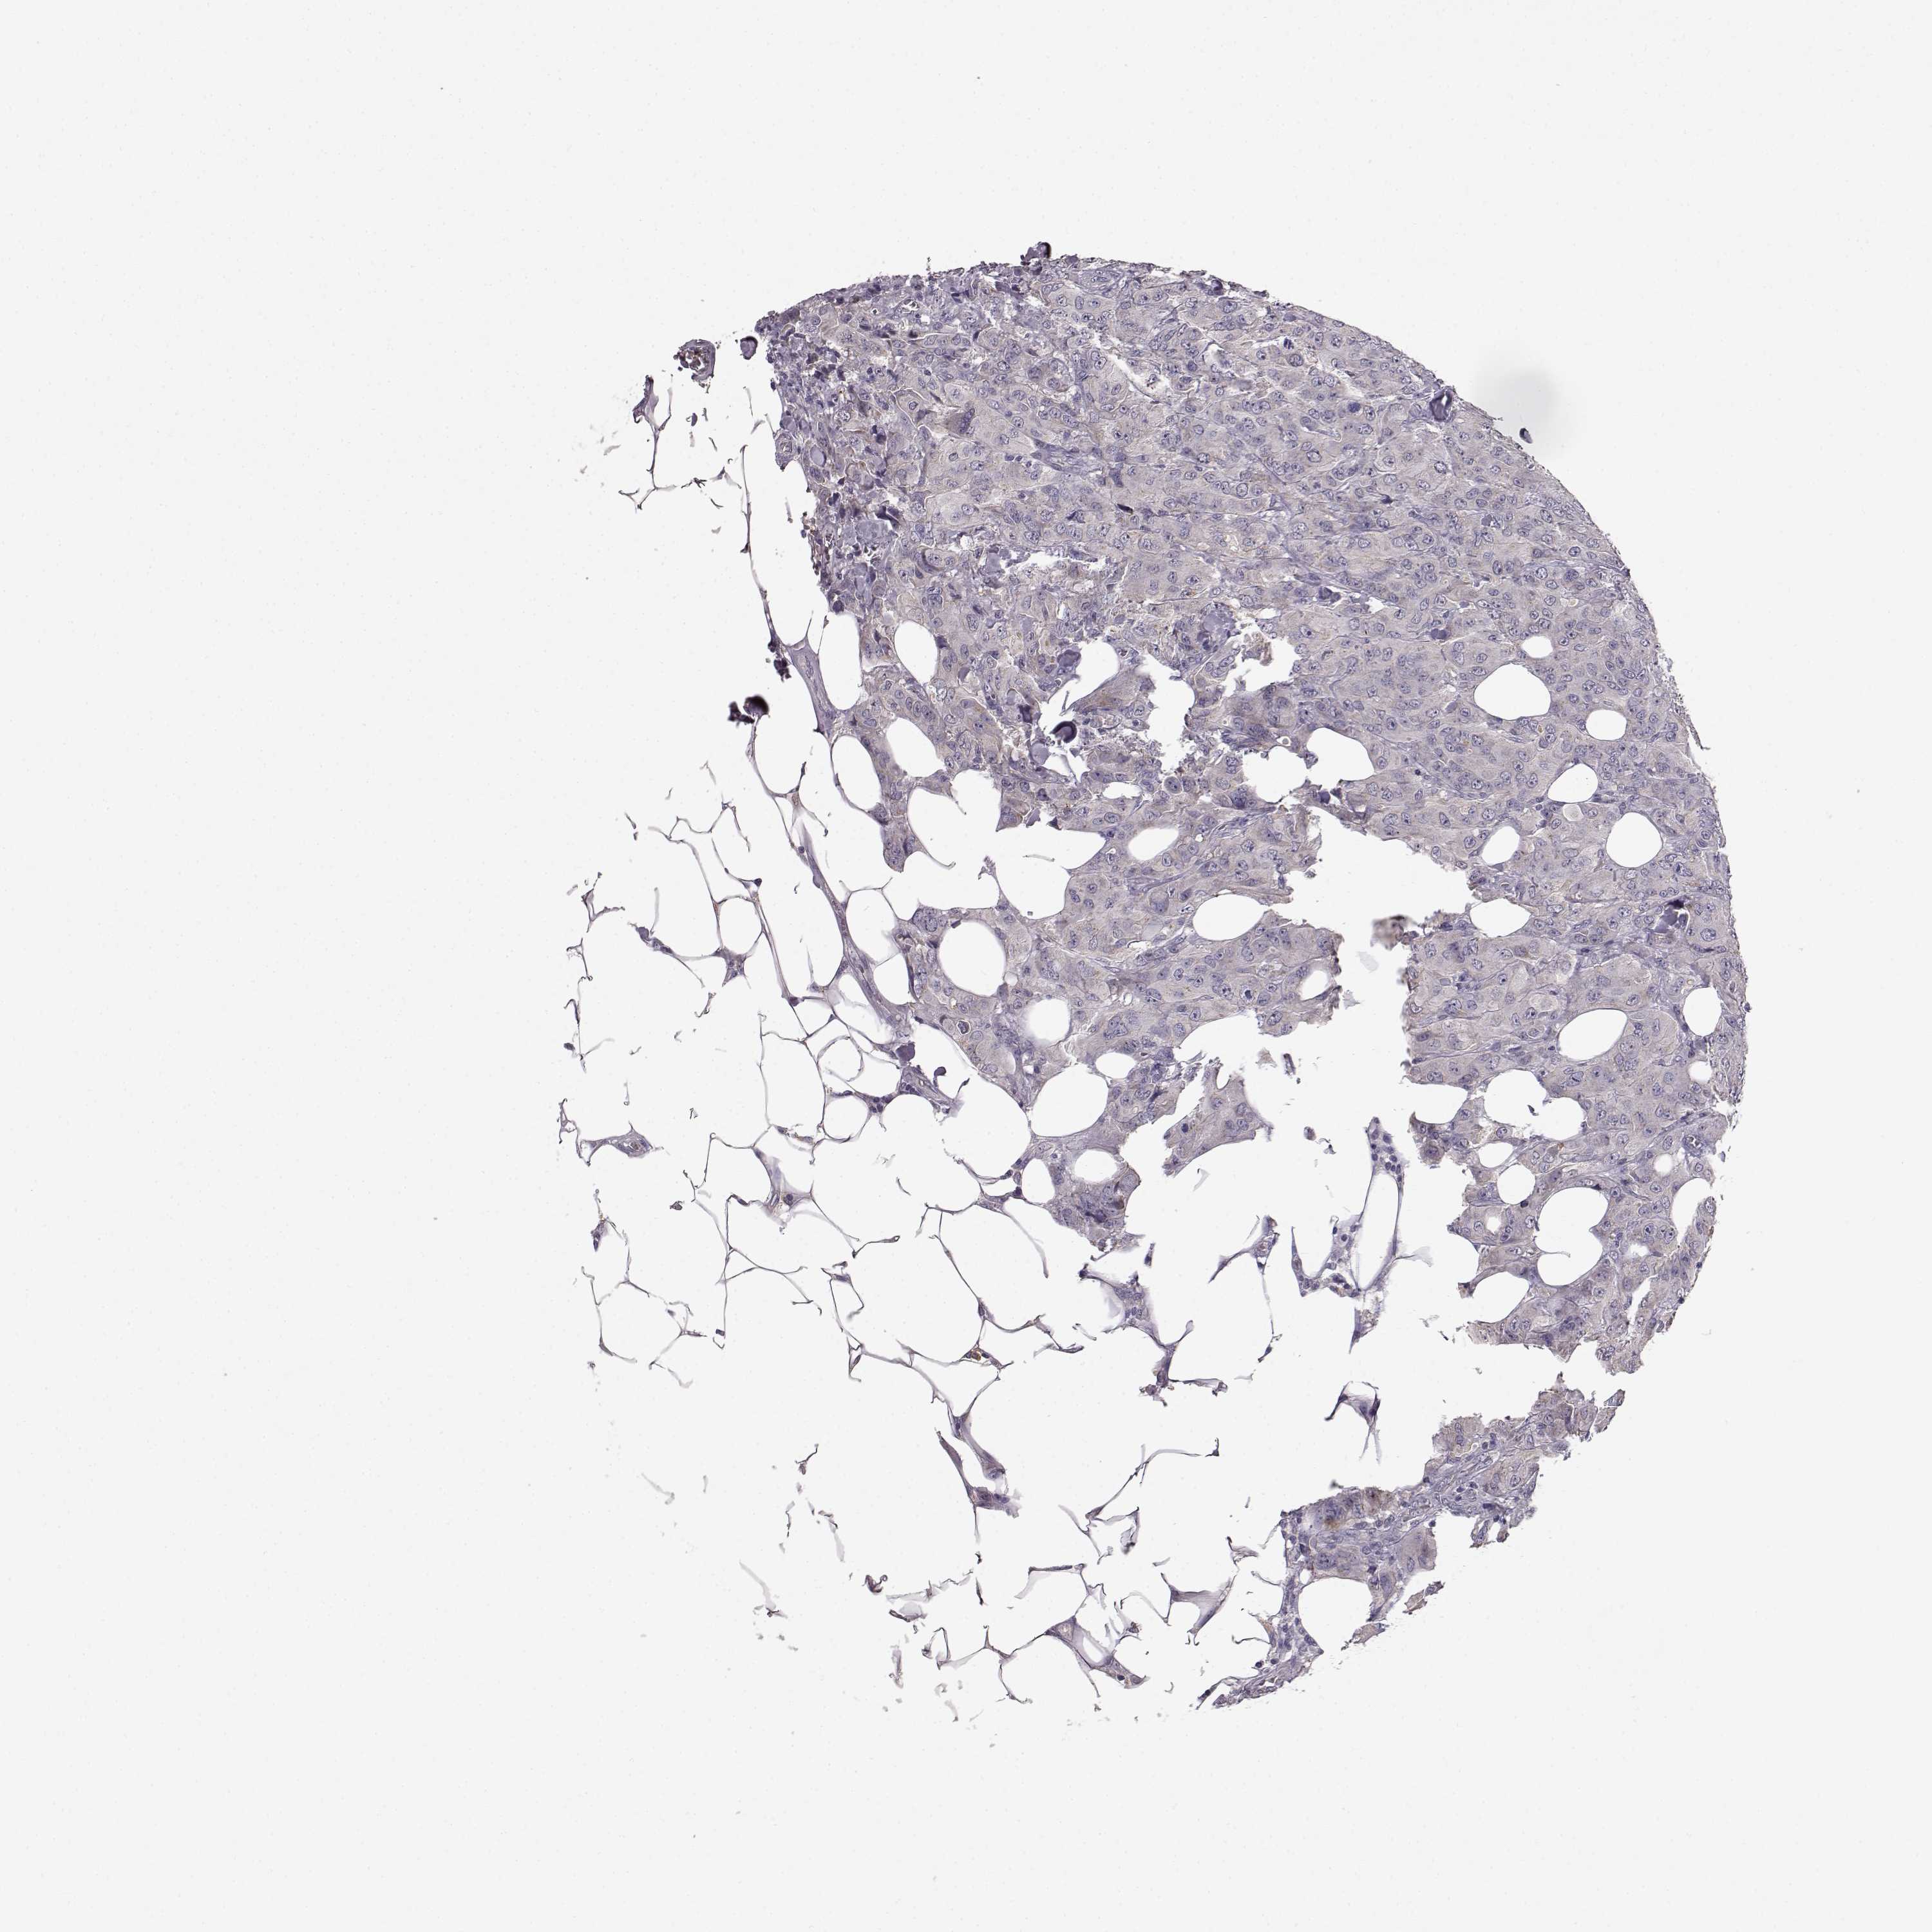

CANCER BREAST CANCER Show tissue menu

BRCA TCGA BRCA VALIDATION PROTEIN EXPRESSION